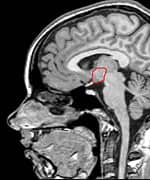

Traumatic brain injury (TBI) is often referred to as the "signature wound" of both the Iraq and Afghanistan wars. Traumatic brain injury occurs when a sudden trauma to the head disrupts brain function. In both these wars, however, even close proximity to the force of an explosion can be just as devastating. Most of the reported traumatic brain injury among Operation Enduring Freedom and Operation Iraqi Freedom veterans has been traced to improvised explosive devices, or IEDs. "Traumatic brain injury can be caused by a direct impact, or by acceleration alone," explains Dr. Mark L. Gordon, interventional endocrinologist and traumatic brain injury treatment specialist at Millennium Health Centers in Los Angeles. "Brain trauma also causes secondary injury, which takes place in the minutes and days following the injury," he adds. "These processes include alterations in cerebral blood flow and increased pressure within the skull, contributing substantially to damage from the initial injury." Gordon says traumatic brain injury can cause a host of physical, cognitive, emotional, and behavioral effects, some of which can be difficult to detect. Symptoms can appear immediately or weeks to years following the injury. "Insidious traumatic brain injury can be difficult to detect," Gordon says. "Localized damage to the frontal and occipital lobes occurs when the brain collides with the skull. Increasingly, we are discovering that traumatic brain injury is also a causative factor for accelerated hormonal deficiencies." These deficiencies, says Gordon, can cause a host of psychological, physiological, and physical manifestations, including depression, outbursts of anger, anxiety, mood swings, memory loss, inability to concentrate, learning disabilities, sleep deprivation, increased risk for heart attacks, strokes, high blood pressure, diabetes, loss of libido, menstrual irregularities, premature menopause, obesity, loss of lean body mass, muscular weakness, and a number of other medically documented conditions. What's more, Gordon points out that veterans suffering from these forms of psychological damage due to traumatic brain injury are frequently misdiagnosed and have their injury erroneously downgraded to post-traumatic stress disorder (PTSD). Moreover, especially in mild traumatic brain injury cases, symptoms at the initial time of injury may go unrecognized or unnoticed, but patients will still develop hormone deficiencies. Unfortunately, the government is slow to accept the link between traumatic brain injury and hormonal deficiencies. Dr. Gordon's Epiphany

Growth Hormone: A Critical PlayerGrowth hormone is the most common hormone deficiency or insufficiency in patients with traumatic brain injury at any level of severity.16-19 Deficiencies in this hormone are especially marked in patients with moderate to severe traumatic brain injury.20 Brain-injured patients with growth hormone deficiency experience rapid weight gain and have substantially lower levels of other hormones as well.17,19 Low growth hormone levels are also associated with excessive anxiety and depression and poor physical health and quality of life.15,21 Finally, brain-injured patients with growth hormone deficiency show greater deficits in attention, executive functioning, memory, and emotion than those with normal growth hormone levels.22 Growth hormone is an intriguing hormone, and we are learning more about it each year. In children, it is responsible for regulating linear growth, ultimately determining adult height and body proportions. But growth hormone has many other remarkable functions throughout the body and into adulthood. It is neuroprotective, increasing survival of damaged nerve cells and promoting regeneration of nerve tissue.23-25 Growth hormone also increases the number of receptors for other hormones in tissues throughout the body; this has the effect of increasing the body's sensitivity to those hormones' actions, helping to overcome the effects of their deficiencies.26-29 Like all hormones, growth hormone acts by binding to specific cell-surface receptors. Receptors for growth hormone are found throughout the brain, and they are especially densely distributed in brain regions responsible for learning and memory.30,31 That may explain why declining growth hormone levels are associated with poorer cognitive function. Growth hormone levels fall with age and are especially low in Alzheimer's disease.32-36 As Dr. Gordon points out, it is therefore not surprising that traumatic brain injury patients often show symptoms identical to the cognitive decline and memory loss we see with aging and Alzheimer's disease. In essence, a brain-injured patient with low growth hormone levels undergoes accelerated cognitive aging. Hope for Traumatic Brain Injury Patients at Millennium Health Centers